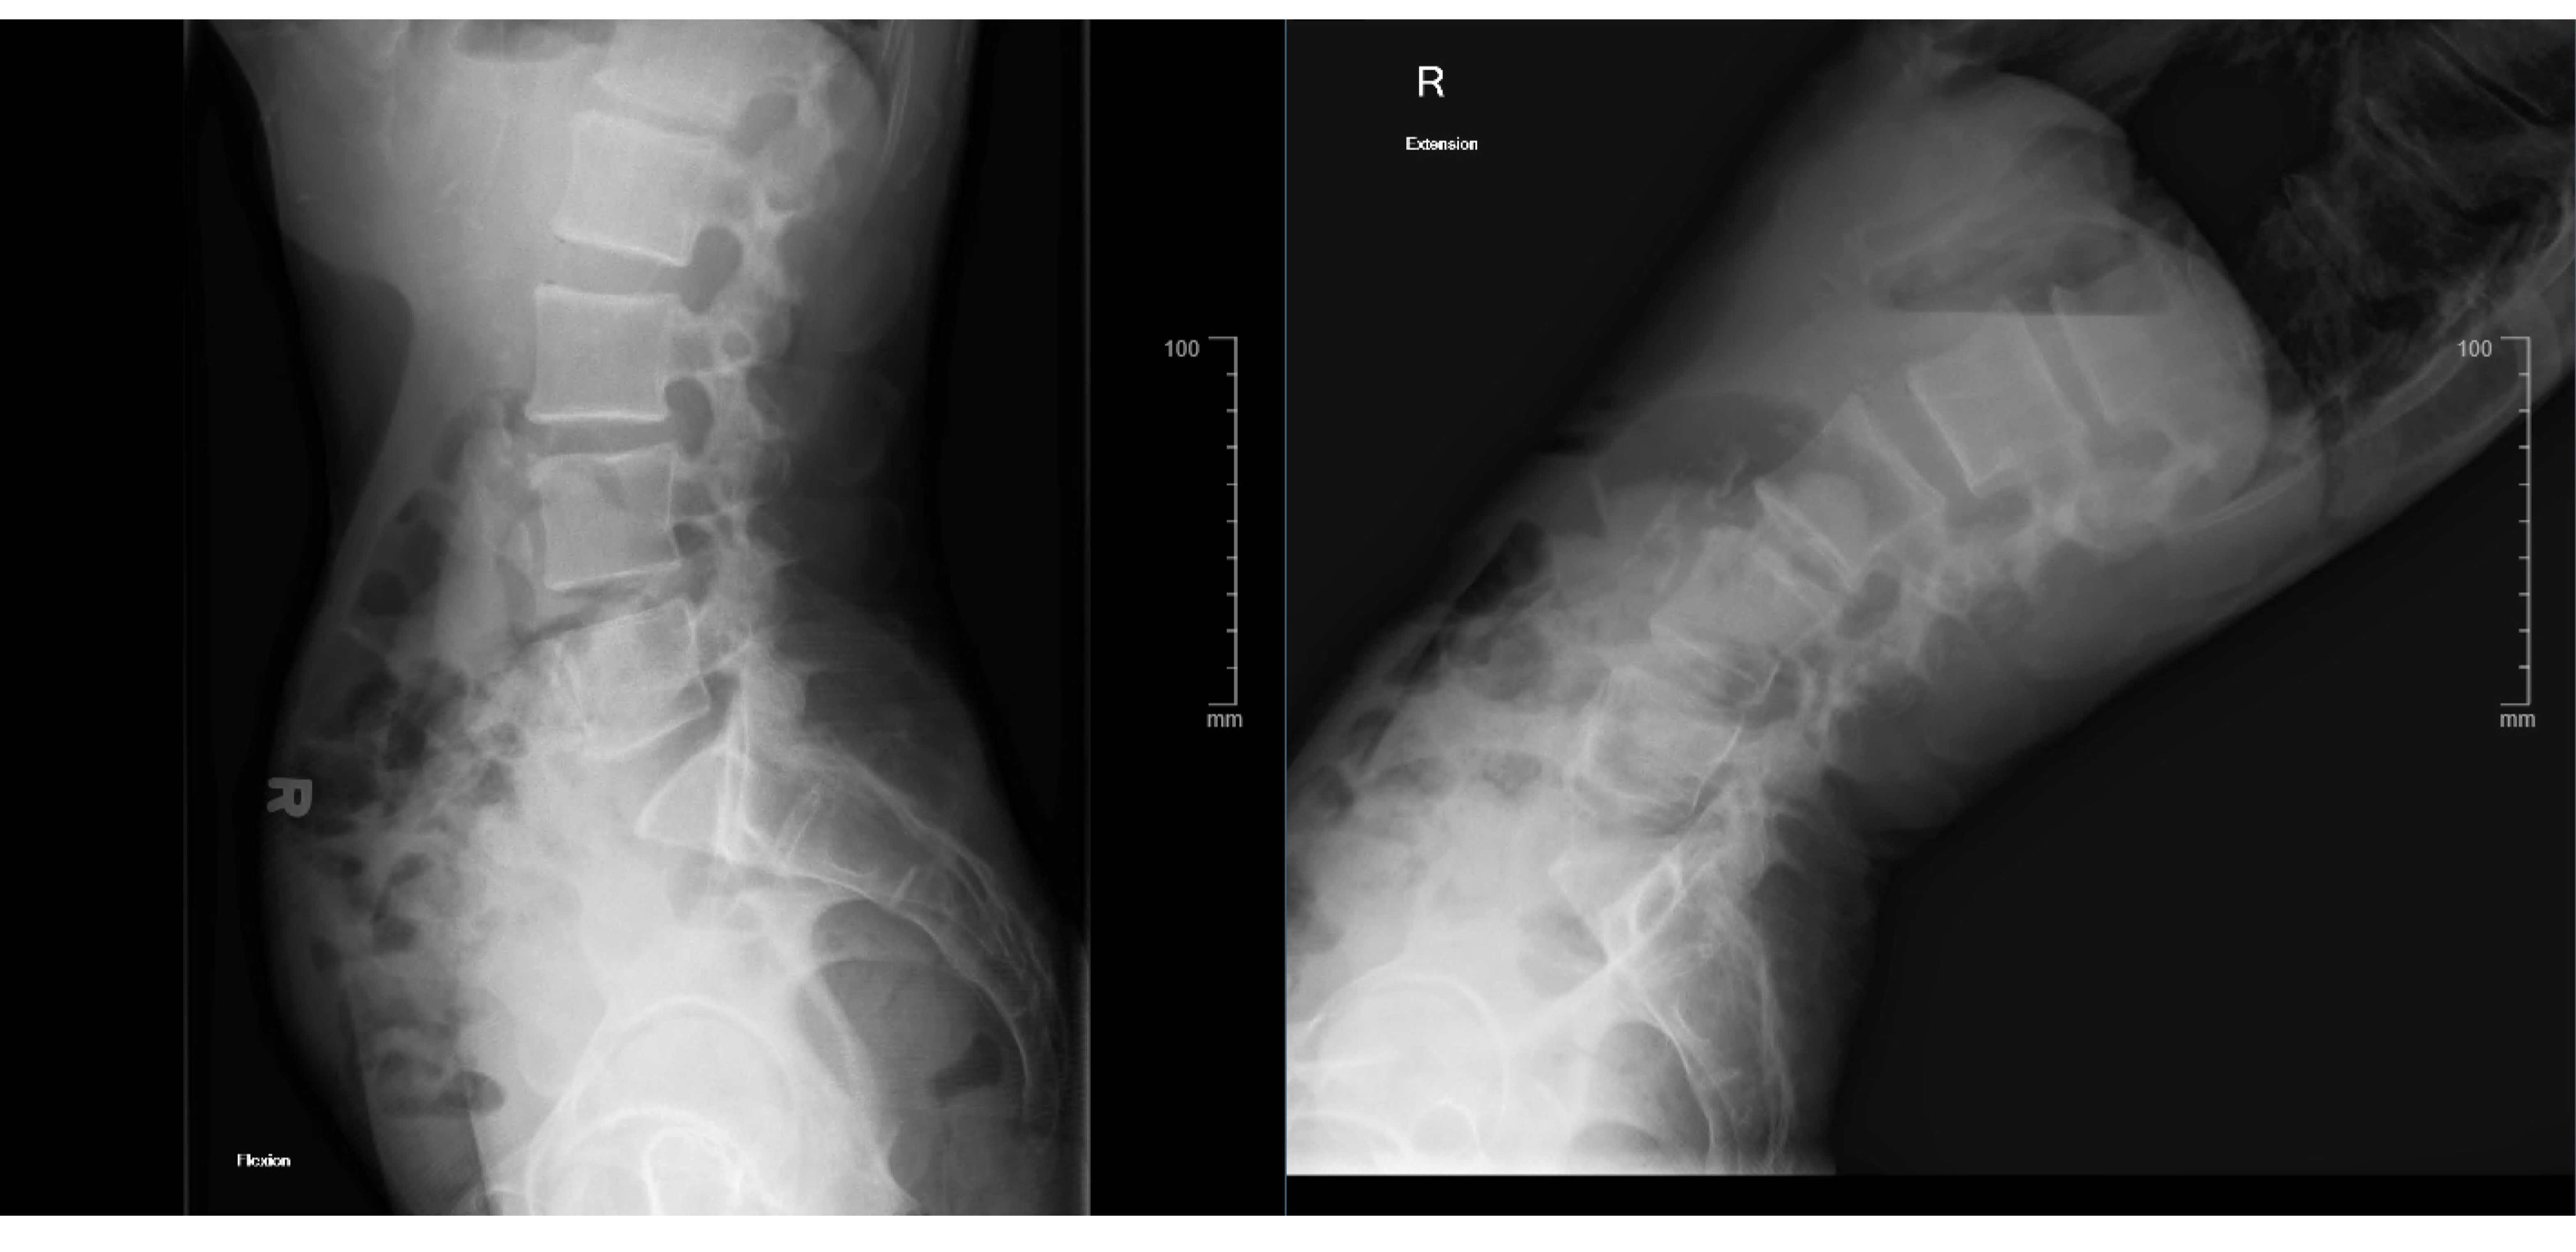

Lumbar flexion-extension films showed no overt instability on the L3–4 spondylolisthesis (Figure 4).

Figure 4. Flexion-extension X-ray showing no overt instability.